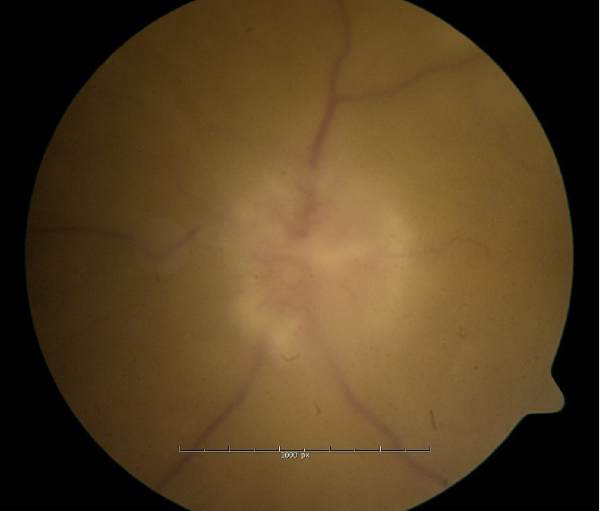

This case report discusses a patient with a history of DLBCL who presented with progressive optic neuropathy despite negative neuro-imaging and cerebrospinal fluid analysis. The case illustrates the limitations of standard CNS surveillance in detecting occult infiltration and highlights the necessity of tissue biopsy for definitive diagnosis.